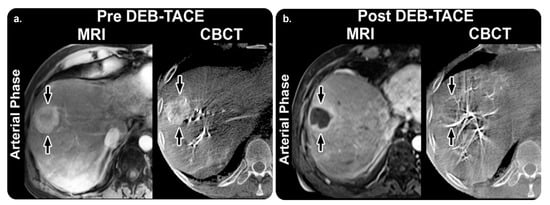

This X-ray acquisition technique enables computed tomography (CT)-like visualization of soft tissue structures periprocedurally; CT-like images aid in soft tissue and bone structure assessments and stent deployment. This technique also guides cone-beam CT (CBCT) image acquisition in a step-by-step manner. Additionally, it enables table-side access to advanced 3D measurements and efficient interaction with CBCT images on a touch-screen module. It also provides open CBCT protocols for liver procedures. SmartCT Soft Tissue can be used in interventional facilities along with a Philips Interventional X-ray system. According to the GMDN, it is an angiographic X-ray system application software [11,12] (Figure 2).

Loffroy et al. [14] conducted a prospective observational study to evaluate whether C-arm dual-phase CBCT helped determine tumor response in 50 targeted hepatocellular carcinomas (HCCs) in 29 patients who underwent transarterial chemoembolization (TACE). Their findings revealed that intraprocedural C-arm dual-phase CBCT could be used to determine HCC response at the 1-month follow-up point.

Figure 2. SmartCT software soft tissue technique and its role in management planning. (a) Arterial-phase images obtained before TACE. MRI revealing a 75 mm mass in the right lobe “arrow” with 65% enhancement. The mass has a similar enhancement (75%) with CBCT. (b) Arterial-phase images obtained after TACE. Mass shows almost no enhancement (5%) with MRI, and the tumor is decreased to 69 mm. With CBCT, the intraprocedural mass enhancement is decreased by 87%, which allows prediction of an objective EASL response at 1 month. Abbreviations: TACE, transarterial chemoembolization; MRI, magnetic resonance imaging; CBCT, cone-beam computed tomography; EASL, European Association for the Study of the Liver. Reprinted from “Intraprocedural C-arm dual-phase cone-beam CT: Can it be used to predict short-term response to TACE with drug-eluting beads in patients with hepatocellular carcinoma?” by Loffroy et al. [14] with written approval from the corresponding author and publisher (Radiology; Copyright 2013).